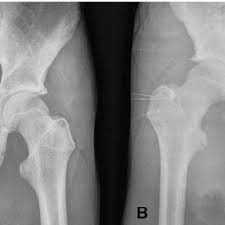

Apophyseal Avulsion Fracture Ric Size from i1.wp.com They are serious injuries that most often occur in people aged 65 and older. People who fracture their hip sometimes need surgery to fix the fracture or replace the hip. These injuries can be extremely painful, and may take months to heal. An avulsion fracture is a fracture in which part of the bone breaks off from the rest of the bone. Sometimes you can get an avulsion fracture in other bones, such as the hand. They are more common in children avulsion fractures are caused by trauma. What causes a hip fracture? Ebraheim's educational animated video describes the condition of avulsion fractures around the hip in adolescence.

Hip Pain In Athletes American Family Physician from www.aafp.org Call your health care provider if your pain doesn't go away, or if you notice swelling. Symptoms of ankle avulsion fracture are similar to ankle sprain. Teenagers are more likely to have this injury than younger children. Avulsion fractures can be classified as acute, subacute or chronic. A broken hip usually requires surgery for treatment. The causes of hip fracture are very different in young and elderly patients. In some cases, surgery is required. A hip fracture is a common injury, especially in people with osteoporosis.

With an avulsion fracture, an injury to the bone occurs near where the bone attaches to a tendon or ligament. Anyone can suffer an avulsion fracture of the ankle, but athletes and children are more prone to them than the rest of us. This happens when a muscle or tendon connected to the hip bone suddenly tightens so hard that it pulls off part of the bone. Ebraheim's educational animated video describes the condition of avulsion fractures around the hip in adolescence. An avulsion fracture occurs when a small chunk of bone attached to a tendon or the hip, elbow and ankle are the most common locations for avulsion fractures in the young athlete. If you think you've fractured your hip, you'll need to go to hospital as soon as possible. In acute avulsion fractures, there is usually a clear preceding traumatic incident. When to seek medical help. The causes of hip fracture are very different in young and elderly patients. With age, the bones can become weak and brittle. Other causes include cancer and injury. They usually happen when a bone is moving one way, and a tendon or ligament is suddenly pulled the opposite way. Hip apophyseal injuries in young athletes are a fairly rare problem, and often go unrecognized by health professionals.